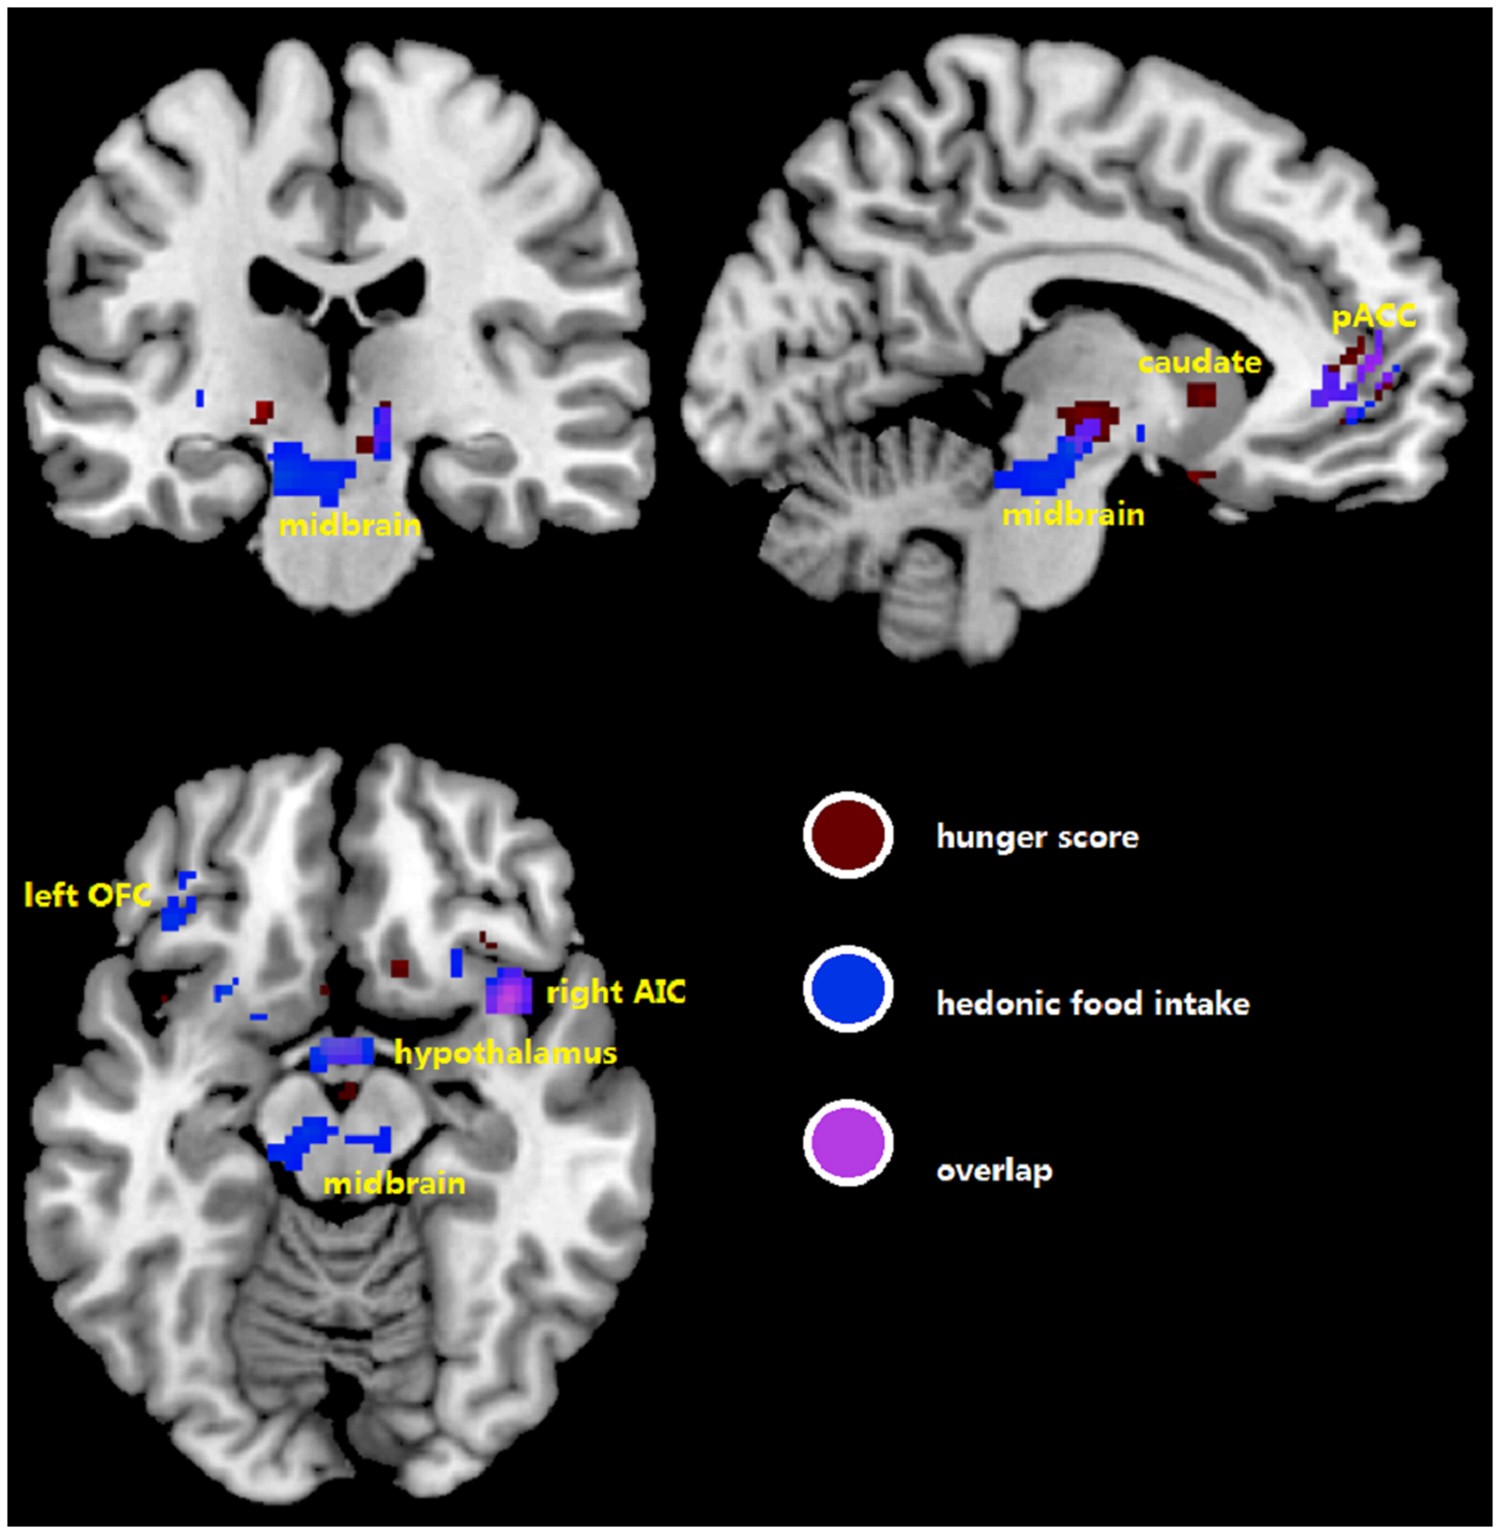

Figure 5

Overview of homeostatic and hedonic brain regions where differential activation by erythromycin compared to saline covaries with differences in hunger ratings (in brown) and hedonic food intake (in blue). pACC, perigenual anterior cingulate cortex; AIC, anterior insular cortex; OFC, orbitofrontal cortex.